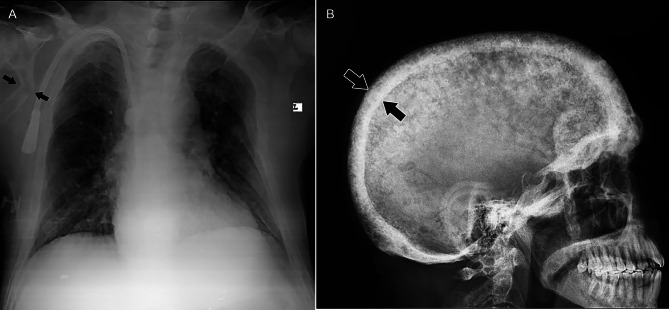

Case presentation: A 42-year-old ESRD patient on HD 3 times a week presented to Shariati Hospital, Tehran, Iran, complaining of worsening bone pain and loss of appetite. Laboratory data revealed an intact parathyroid hormone (iPTH) concentration of 2500 pg/mL, an alkaline phosphatase (Alp) level of 4340 IU/L, a phosphorus (P) level of 9 mg/dL, and a calcium (Ca) concentration of 7.2 mg/dL. Sestamibi scintigraphy revealed parathyroid adenoma. The findings suggested tertiary hyperparathyroidism (HPT-III), and the patient was scheduled for total PTX. Approximately one month after surgery, the patient was referred due to convulsions, leg mobility problems, and worsening bone pain. There was bilateral femoral ecchymosis. The Ca concentration was 5.8 mg/dL, and radiological evaluations revealed multiple skeletal fractures. HBS after PTX was suggested for this patient. After several days of hospitalization, he suffered subcutaneous emphysema followed by rib fractures and passed away.